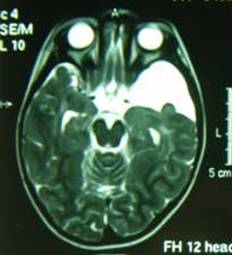

Tedavisi cerrahi girişimdir. Kistin şantlanması (Resim 5), her iki yan karıncığın şantlanması ve açık cerrahi denenmiş yöntemlerdir. Kistin şantlanması körlemesine bir yöntem olduğundan kolay olmayıp her zaman kistin içine girmek kolay değildir. Açık cerrahide her

Resim 5: BTde şant ameliyatı uygulanmış suprasellar kist görüntüleri görülmektedir. (®) şant kateterini göstermektedir.

zaman başarılı sonuç elde etmek mümkün değildir ve büyük bir cerrahidir. Günümüzde suprasellar araknoid kistlerin tedavisinde ilk seçenek endoskopik girişim olmalıdır. Kafatasında küçük bir delikten endoskop ile girilerek kist karıncıklar ve BOS yolları ile ağızlaştırılır (Resim 6). Endoskopik girişimlerde başarı %90’ın üzerindedir. Başarısız olan olgularda şant cerrahisi yapılmalıdır. Tedavinin gecikmediği hastalarda sonuçlar iyidir ve hastalar normal yaşamlarına devam ederler.

Resim 6: (a) ve

(b) yatay ve dikey düzlemlerdeki MRG görüntülerinde üçüncü karıncığı dolduran ve yan karıncıkların genişlemesine neden olan suprasellar araknoid kistin ameliyat öncesi görüntüleri,

(c) ve

(d) endoskopik ameliyat sonrası kistin küçüldüğü ve yan karıncıklardaki genişlemenin azaldığı izlenmektedir.